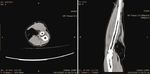

A CT and MRI with contrast demonstrated a well-encap-                    Figure 1: Preoperative view of the patient’s forearm.

sulated, solid multilobular lesion with lipoid content and the

presence of septa (Figures 2 and 3). The enhancement of the                 At present, the WHO Classification of Soft Tissue

septa demonstrated the rich vascularity of the lesion. There           Tumors classifies angiolipomas in the group of adipocytic

were no signs of infiltration of the surrounding tissues. The           tumors, the largest group of mesenchymal tumors (the same

dimensions of the lesion were 4:8 × 4:7 × 7:03 cm. The find-            as lipomas, liposarcomas, etc.) [8]. It is described as a benign

ings suggested a lipoma, but the imaging could not exclude             soft tissue tumor subdivided into infiltrative and noninfiltra-

a sarcomatous transformation due to the presence of septa              tive types. The rare infiltrative, nonencapsulated type typi-

and of the dishomogeneity of the signal’s density.                     cally involves deep soft tissues and is separated from the

Figure 2: CT scans.